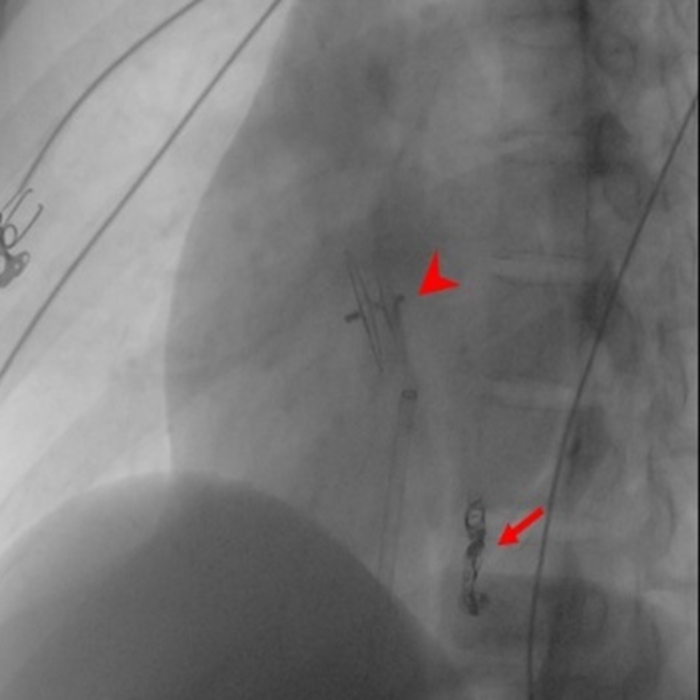

针对患者的情况,闫朝武带领柳昂、齐晨医师,在充分评估病变特征和手术路径的基础上,决定采用同步封堵的策略。术中,团队凭借娴熟的介入技术,通过微创穿刺,精准地将导丝和导管分别送至两处病变位置,并顺利实施封堵。术后即刻复查造影显示,封堵器形态良好、位置稳定,异常分流消失。患者术后恢复良好,头痛症状完全消失。